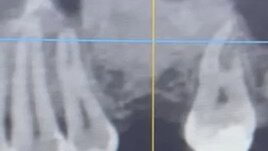

#Синуслифтинг. Продолжение к нижнему посту...Подняли высоту кости. Увеличение высоты идет через боковое окно на верхней челюсти путем отслаивания внутренней мембраны и конденсации искуственной кости.